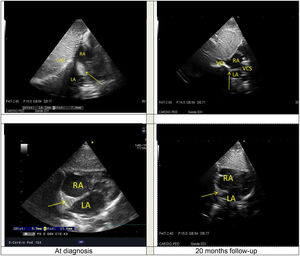

Follow-up at 24-months showed a good clinical evolution, with slow disappearance of the cardiac mass, with negativation of VDRL. TPHA rates remained positive and stable over the course of the evolution. The boy showed good psychomotor development and growth. No other signs of syphilis were found. The intracardiac mass disappeared at the 20-month follow-up echocardiography (Fig. 3Figure 3).